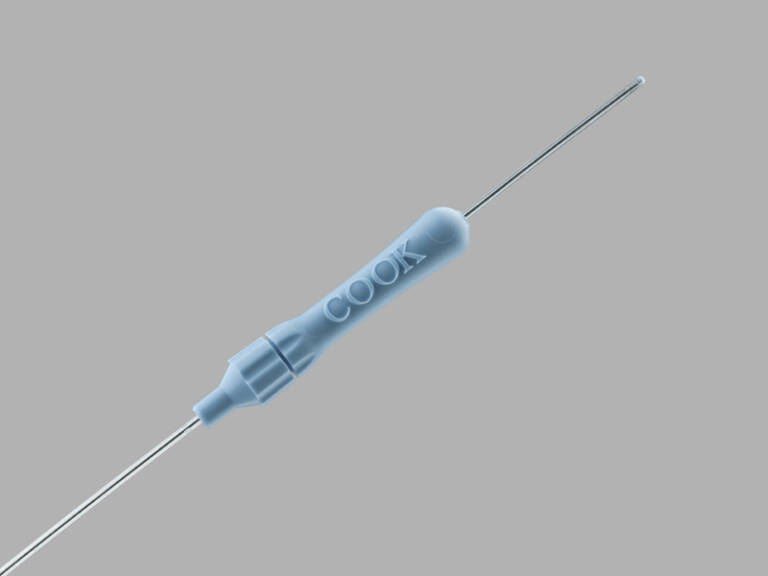

Cook® Obturator

DESCRIPTION:

Used to supplement and assist uterine access of a cleared, dimensionally compatible embryo transfer device for placement of in vitro fertilized (IVF) embryos into the uterine cavity.

- The adjustable length works with a variety of Cook Medical and other embryo transfer catheters.

- The hub locks in place.

ADDITIONAL INFORMATION:

| Catalog number | Diameter, Fr | Length, cm |

| J-UOB-4028 | 4.0 | 28 |